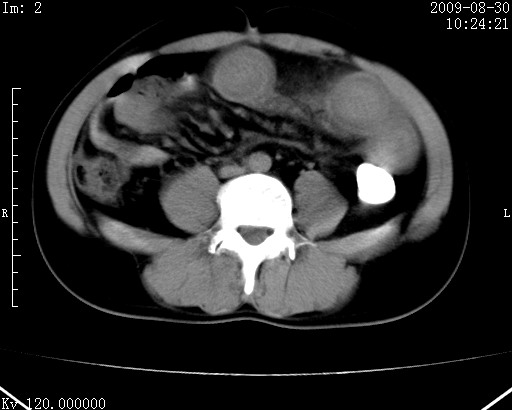

患者唐某,男31岁,已婚,本地务农。

自述入院前两天一次进食较多冷饮之后,出现阵发性上腹部疼痛,次日加剧伴恶心、呕吐,呕吐后症状稍减轻。食欲差。大便每天1-2次,量少,暗红色水样。小便赤。无畏寒、发热、咳嗽等呼吸道症状。无高血压及胃病史。

检查:体温、血压及脉搏正常.皮肤无黄染,浅表无淋巴结肿大。左腹肌紧张,左上腹有压痛,无反跳痛,可触及包块。

生化:钾、钠、氯、钙、ph正常,总胆红素和直接胆红素稍高,空腹血糖稍高。

尿淀粉酶:1256 u/l(正常60-401)。

血常规:wbc 22.4x109/l gr88% ly9.6%其余基本正常。

胃镜:急性胃炎。立位腹平片:未见异常。

下面是ct平扫,降结肠内是对比剂。

术前影像诊断:上段空肠急性缺血性坏死并腹水。建议手术治疗。

术中见上段空肠约70cm长范围坏死,从屈氏韧带远端约10cm处开始。坏死肠管肿胀变形变色,管壁明显环形增厚,部分聚成大肿块,无扭转和套叠。肠系膜上动脉分支内广泛泥沙状血栓。肠切除。

临床诊断:肠系膜上动脉梗塞并急性肠坏死。

开始时我们科也有人认为是套叠,最后统一意见,不考虑肠套。我们看到的“靶征”,“晕圈征”,“双圈征”实际上只是单根肠管的横断面。坏死肿胀后肠壁各层的密度不一样。

左侧腹小肠腔管壁明显增厚,部分内示靶征,走行异常,部分肠系膜绳样改变,肝包膜下及肠间较多液体密度,然梗阻近端肠腔积气不明显。

考虑;肠扭曲伴肠坏死。